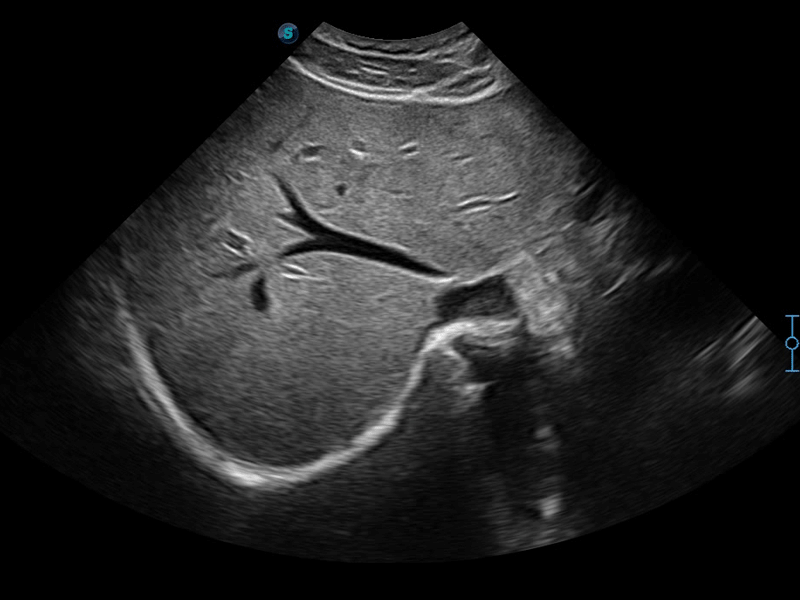

实时宽景成像技术

通过彩色血流和实时宽景相结合,可观察到完整的动静脉血流,方便医生检查。实时扫查过程中,如有任何操作失误也可以很容易地进行回扫擦除,而不会中断扫查。